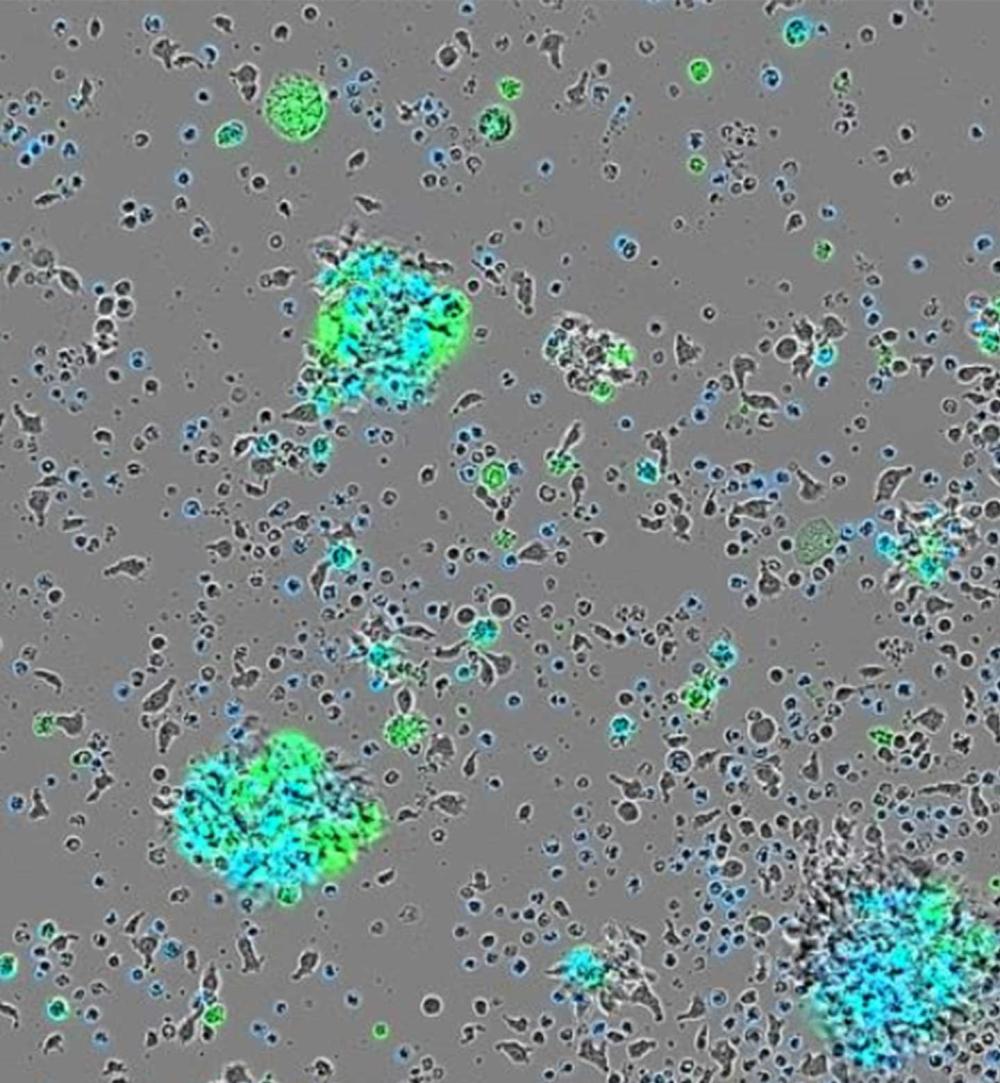

Scientists Create Cancer-Fighting Immune Cells Right in the Body

A new form of CAR T kills leukemia, multiple myeloma, and sarcoma in mice, opening the door to a future off-the-shelf cancer treatment without chemotherapy.